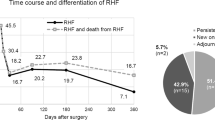

RVF was strongly associated with survival as shown by the Kaplan–Meier curves (p = 0.003) (Fig. 1) and the Cox proportional risk model [HR 3.42 (95% CI 1.41–8.16) p = 0.01]. RVF patients showed a 30-day survival of 25% compared to 77% in non-RVF patients, and only 1 out of 8 patients in the RVF group survived up to 3 years.

Finally, our study confirms the strong impact of RVF on early mortality: all patients in which RVF occurred developed this complication in the immediate postoperative period. Comparing the Kaplan–Meier curves of the two groups, a significant survival difference emerged, already after the first month of LVAD placement.